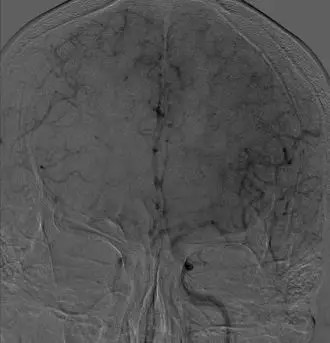

3. 颈内动脉C1段支架植入。

颈内动脉DSA提示颈内动脉狭窄,远端血流较差。 颈内动脉置入9mm-40mm Protege支架,收回保护伞后DSA提示血管再通良好,给予替罗非班7ml/h。 术后即刻查体NIHSS评分8分,给予替罗非班10ml/h泵入,持续24h。 术后第2天复查灌注成像提示双侧半球基本对称,CTA提示右侧颈内动脉以及大脑中动脉通畅。

术后结论 右侧颈内动脉C1段闭塞合并右侧MCA上干闭塞,M2远端分支闭塞以及MCA下干起始段局部血栓形成。 术后随访 术后3月mRS评分:1分。